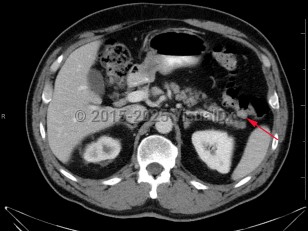

Imaging Studies image of Colonic polyps - imageId=7904556. Click to open in gallery.  caption: '<span>Axial CT image demonstrates a  soft tissue density at the splenic flexure. Subsequent colonoscopy  findings were consistent with colonic polyp.</span>'

Axial CT image demonstrates a soft tissue density at the splenic flexure. Subsequent colonoscopy findings were consistent with colonic polyp.